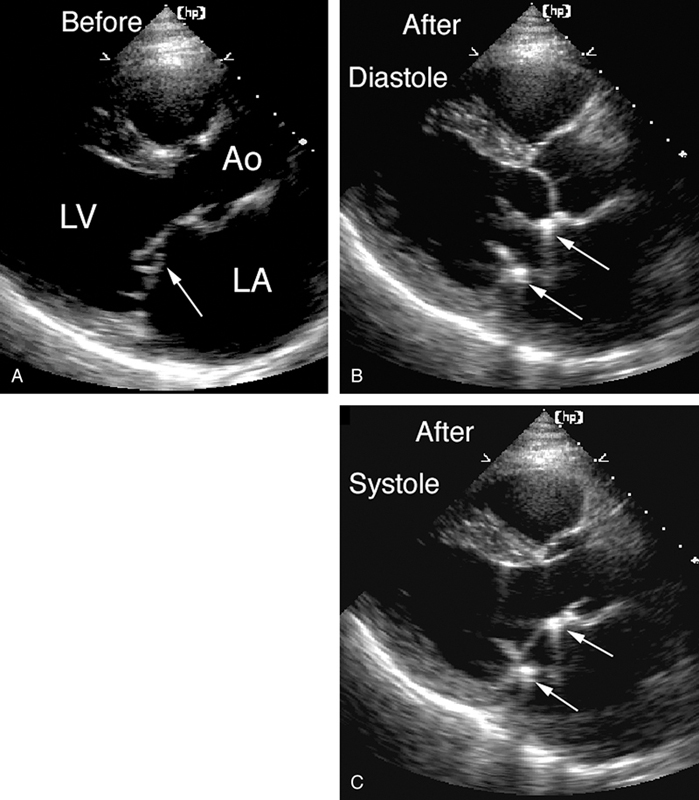

فحوصات تشخيصية لبعض امراض القلب والشرايين التاجية